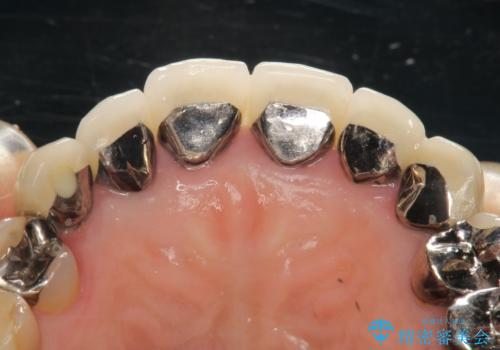

- 下顎の前歯に激痛を覚えて来院された患者様です。

取り急ぎ下顎前歯数歯の根管治療を、銀座しらゆり歯科医院長の林先生にお願いし、それ以外に気になっている、不自然な色調のクラウン、金属部分が見えてブラッシングがしにくいインプラント補綴、口元の突出感、出血のしやすい歯周ポケットなど、全てを解決するための治療を行うこととしました。